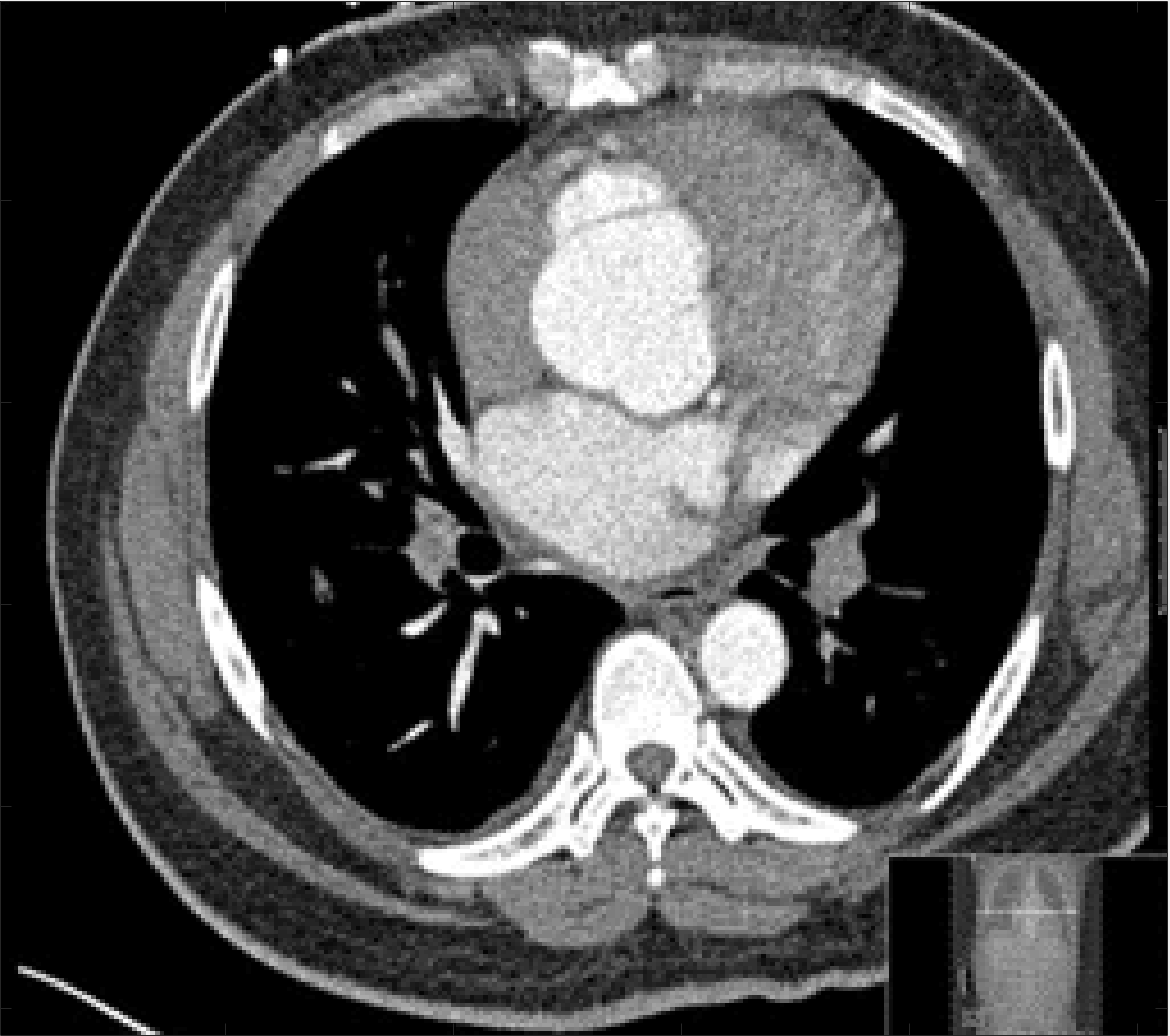

Four sets of test results are shown below. In Test 1 we compare models M1 – M6 to the proposed model M7 for two images which are hard to segment. The first is a CT scan from which we would like to segment the lower portion of the heart, the second is an MRI scan of a knee and we would like to segment the top of the Tibia. See Figure 9 for the test images and the marker sets used in the experiments. In Test 2 we will review the sensitivity of the proposed model to the main parameters. In Test 3 we will give several results achieved by the model using marker and anti-marker sets. In Test 4 we show the initialisation independence and marker independence of the Geodesic Model on real images.

In this test we give the segmentation results for models M1 – M7 for the two challenging test images shown in Figure 9. The marker and anti-marker sets used in the experiments are also shown in this figure. After extensive parameter tuning, the best final segmentation results for each of the models are shown in Figures 10 and 11. For M1 – M4 we obtain incorrect segmentations in both cases. In particular, the results of M2 and M4 are interesting as the former gives poor results for both images, and the latter gives a reasonable result for Test Image 1 and a poor result for Test Image 2. In the case of M2, the regularisation term includes the edge detector and the distance penalty term (see (4)). It is precisely this which permits the poor result in Figures 10(b) and 11(b) as the edge detector is zero along the contour and the fitting terms are satisfied there (both intensity and area constraints) – the distance term is not large enough to counteract the effect of these. In the case of M4, the distance term and edge detector are separated from the regulariser and are used to weight the Chan-Vese fitting terms (see (9)). The poor segmentation in Figure 11(b) is due to the Chan-Vese terms encouraging segmentation of bright objects (in this case), weighting enforces these terms at all edges in the image and near . In experiments, we find that M4 performs well when the object to segment is of approximately the highest or lowest intensity in the image, however when this is not the case, results tend to be poor. We see that, in both cases, models M5 and M6 give much improved results to M2 and M4 (obtained by incorporating the geodesic distance penalty into each). The proposed Geodesic Model M7 gives an accurate segmentation in both cases. It remains to compare M5, M6 and M7. We see that M5 is a non-convex model (and cannot be made convex [39]), therefore results are initialisation dependent. It also requires one more parameter than M6 and M7, and an accurate set to give a reasonable area constraint in (4). These limitations lead us to conclude M6 and M7 are better choices than M5. In the case of M6, it has the same number of parameters as M7 and gives good results. M6 can be viewed as the model M7 with weighted intensity fitting terms (compare (18) and (30)). Experimentally, we find that the same quality of segmentation result can be achieved with both models generally, however M6 is more parameter sensitive than M7. This can be seen in the parameter map in Figure 12 with M7 giving an accurate result for a wider range of parameters than M6. To show the improvement of M7 over previous models, we also give an image in Figure 13 which can be accurately segmented with M7 but the correct result is never achieved with M6 (or M3). Therefore we find that M7 outperforms all other models tested M1 – M6.

Test 3 – Further Results from the Geodesic Model M7. In this test we give some medical segmentation results obtained using the Geodesic Model M7. The results are shown in Figure 14. In the final two columns we use anti-markers to demonstrate how to overcome blurred edges and low contrast edges in an image. These are challenging and it is pleasing to see the correctly segmented results.